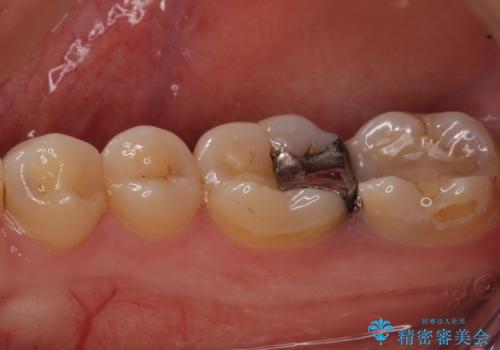

- 右上下の奥歯がむし歯でしみたり痛んだりするとのことで来院された患者様です。

下顎の奥歯は強い痛みを感じており、既に歯髄に不可逆的な炎症が起きていると診断されたため、根管治療の後にセラミッククラウンにて補綴治療を行うこととしました。

上顎の奥歯は最近銀歯による治療を行ったとのことでしたが、適合が不十分であり隙間からしみていたため、適合の良いゴールドインレーにて修復治療を行うこととしました。

下顎のむし歯は歯肉の中にまで及んでいたため、一部歯槽骨を削除し、歯肉縁上に健全歯質が位置するよう外科処置を併用しました。